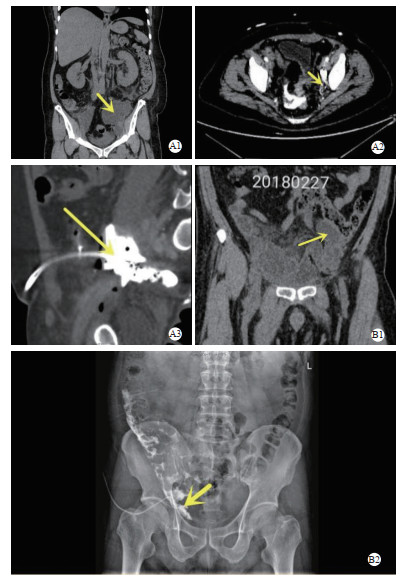

13例患者从发病至囊肿穿刺引流的平均时间为33 h,有2例分别在发病52和53 h后才实施穿刺。最终转归有5例发展为MODS转入ICU,其中4例好转,1例死亡;有2例患者病情反复难以控制,表现为退热后再度发热、腹痛位置变化、新发尿频尿急等症状和感染指标的波动;经影像学检查证实脓腔和周围脏器连通,其中1例为子宫内膜癌患者,感染的淋巴囊肿经引流管贯通乙状结肠穿孔感染,需紧急行腹腔镜下肠穿孔修补术;影像学同时发现患者肾积水,尿检提示尿路感染;1例为膀胱癌患者,淋巴囊肿经引流管贯通回肠新膀胱,病原学培养结果随之发生改变;追踪随访发现救治成功出院的12例患者中仅1例通过B超引导下对残留的较大的淋巴囊肿(最大长径7 cm)进行穿刺抽液引流,后未再发生感染;余11例未作干预的患者中有4例再发囊肿感染1~2次,其中2例合并脓毒性休克,1例死亡,见表 2和图 1。

| A1-3:病例11子宫内膜癌术后患者A1:盆腔淋巴囊肿并感染;A2-3脓腔和乙状结肠连通;B1-2:病例8膀胱癌回肠新膀胱术后患者B1:盆腔囊肿并感染;B2脓腔和回肠代新膀胱连通 图 1 两例脓腔和附近器官连通影像学表现 Fig 1 Imaging features of the connections between the infected lymphocyst and surrounding organs in two patients |